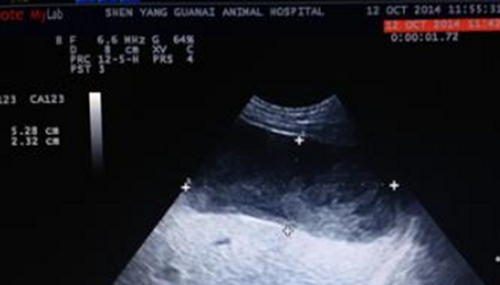

库兴氏综合征是是一种由于垂体或肾上腺病变导致肾上腺皮质分泌过量的糖皮质激素所致的疾病,又称皮质醇增多症。是由于各种原因引起的肾上腺糖皮质激素慢性分泌过多,表现为肥胖伴有高血压等一系列症状。